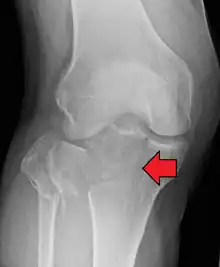

• Type II = Lateral tibial plateau fracture with depression,

This is a combined cleavage and compression fracture and involves vertical split of the lateral condyle combined with depression of the adjacent load bearing part of the condyle. Caused by a valgus force on the knee; it is a low energy injury, typically seen in individuals of the 4th decade or older with osteoporotic changes in bone. Most common, and make up 75% of all tibial plateau fractures. There is a 20% risk of distraction injuries to the medial collateral ligament. May include distraction injury to the medial collateral ligament or anterior cruciate ligament.

Lateral Tibial Plateau fracture XRay with Depression